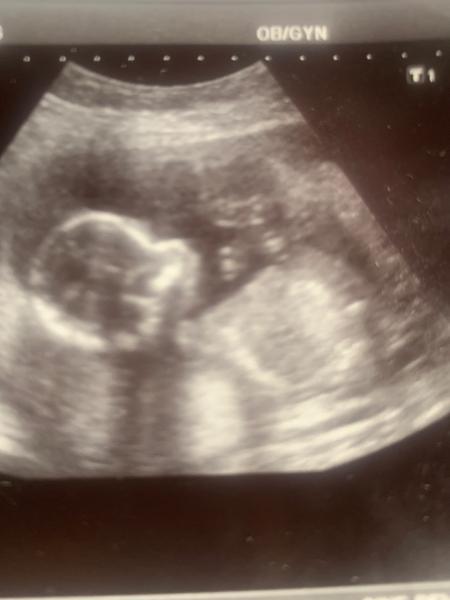

Zdravím holky. Našla jsem tuhle diskuzi a jdu si pro radu.

Foto 17tt ze screengu, ještě 20tt na screeningu mi řekl že kluk. Jenomže v pátek jdu opět je svému doktorovi 27tt a on že holka a trvá na tom od začátku. Hledal, udělal mi 4 fotky a pinďa prostě nikde!!! Je možné, že to pinďa nebyl??? Děkuji za názor